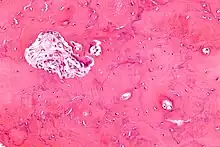

Initially, there is a marked increase in the rate of bone resorption in localized areas, caused by large and numerous osteoclasts. These localized areas of pathological destruction of bone tissue (osteolysis) are seen radiologically as an advancing lytic wedge in long bones or the skull. When this occurs in the skull, it is called osteoporosis circumscripta. The osteolysis is followed by a compensatory increase in bone formation induced by the bone-forming cells, called osteoblasts, that are recruited to the area. This is associated with accelerated deposition of lamellar bone in a disorganized fashion. This intense cellular activity produces a chaotic picture of trabecular bone ("mosaic" pattern), rather than the normal linear lamellar pattern. The resorbed bone is replaced and the marrow spaces are filled by an excess of fibrous connective tissue with a marked increase in blood vessels, causing the bone to become hypervascular. The bone hypercellularity may then diminish, leaving a dense "pagetic bone," also known as burned-out Paget's disease. A later phase of the disease is characterized by the replacement of normal bone marrow with highly vascular fibrous tissue.[24]